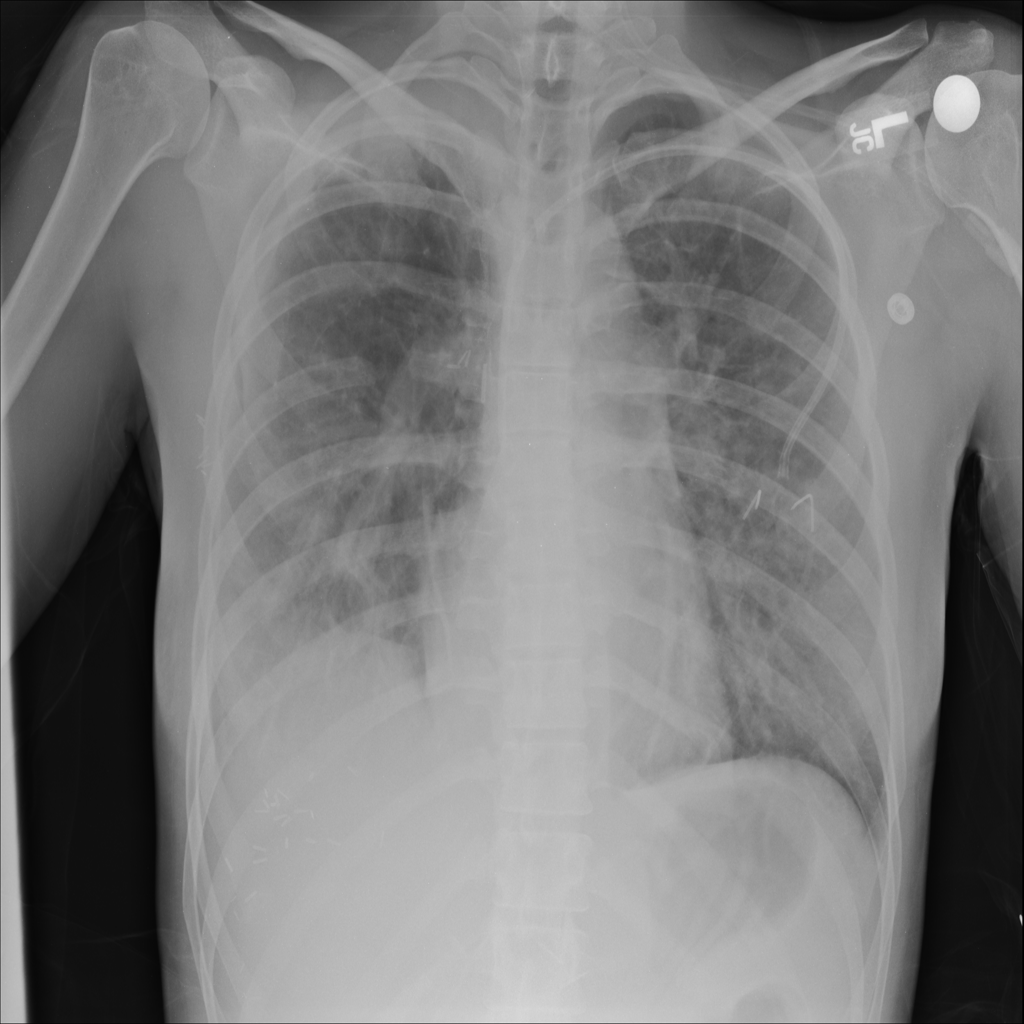

PAT-5B86 · IMG-009Edema

PAT-5B86 · IMG-009

PA